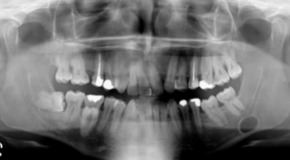

Q

What is the best diagnosis for the pano below?

A

Static bone cyst